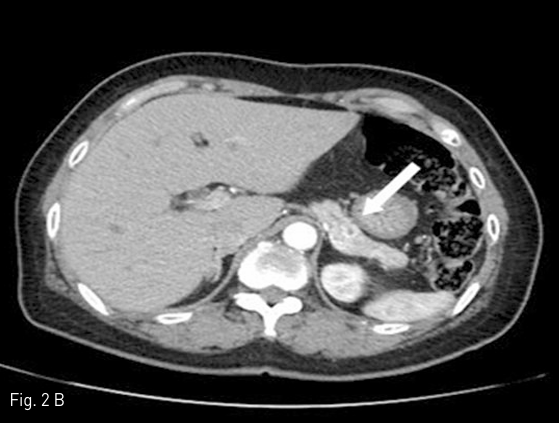

진단 위해 시행한 pancreas dynamic CT 상 pancreas tail 부분에 6mm size 이하의 multiple enhancing lesions이 보여 R/O neuroendocrine tumor 하에 (Fig. 2), insulinoma의 감별진단 및 localization을 위해 arterial stimulation with venous sampling (ASVS)를 시행함.

Fig 2B

Pancreatic dynamic CT images show multiple small, hypervascular tumors in pancreatic body (arrow in A) and tail (arrow in B) portion.